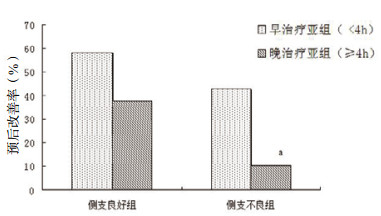

对于侧支循环良好的脑梗死患者,再通治疗延长至4 h以后仍有较好的效果,治疗时间 < 4 h和≥4 h两组患者的预后改善率差异无统计学意义(58.3% vs. 37.8%, χ2=2.463, P=0.117);而侧支循环不良患者受治疗时间影响较大,4 h以后接受再通治疗的脑梗死患者,预后改善率明显低于治疗时间 < 4 h的患者(42.9% vs. 10.5%, P=0.047),见图 2。

|

| 在相同侧支状况组内,与早治疗亚组比较,aP<0.05;侧支不良组总例数33, 其早、晚治疗亚组分别为14例、19例,两者比较采用Fisher精确概率法 图 2 不同侧支循环状况患者的预后受再通时间的影响 Figure 2 Effects of recanalization treatment time on the prognosis of patients with different collateral circulation |

|

|

目前研究一般认为再通治疗时间与脑梗死预后密切相关,患者越早被开通堵塞血管预后越好。2004年4项国际多中心研究汇总分析显示:脑梗死患者于1.5 h、1.5~3 h、3~4.5 h接受rt-PA治疗与接受安慰剂相比,预后良好率提高但随时间延长而逐步下降,3个时间段的OR值分别为2.81(95%CI:1.75~4.50)、1.55(95%CI:1.12~2.15)、1.40(95%CI:1.05~1.85)[8]。随后的研究也得出类似结论[20-21]。不过在本研究中,多元回归分析却未显示治疗时间对预后有显著影响。为探究原因,本课题组进一步将患者依据侧支循环优劣分为两组,分别研究两组患者预后受治疗时间早晚的影响。结果发现,侧支循环良好患者即使延迟至4 h后接受治疗仍有较好预后改善率,与4 h内差异无统计学意义;对于侧支循环不良患者,4 h内治疗组预后改善率同样尚可,而4 h后则明显下降,此时尽管在时间窗内,但鲜有预后改善者。根据以上结果,可推测本研究的多因素分析与以往报道不一致的可能原因:本研究的样本量相对不足,同时其中侧支循环不良者占比可能和以往研究也有差异。

对图 2结果可做出如下思考:对于侧支循环良好的脑梗死患者, 在时间窗之后可能仍有再通治疗指征;而如果患者侧支循环不良,对再通治疗时间要求将更为急迫,若再通时间偏晚(如 > 4 h),即使在时间窗内可能仍难有神经功能改善。有研究就曾根据CTA区分脑梗死患者的侧支循环优劣,发现其中侧支良好者的介入治疗时间窗可以适当延长[22]。可能的机制为,脑梗死发生时,血液可经良好的侧支循环向缺血半暗区输入,增强其缺血耐受性,为再通治疗争取时间并使更多的神经细胞存活。在恢复期随着新生血管逐渐长入,这些细胞将代偿性地发挥更多作用[23]。仅由侧支循环的差异就可得知,脑梗死患者对缺血的耐受时间是千差万别的,目前一刀切的再通治疗时间窗(静脉溶栓4.5 h内、血管内取栓治疗6 h内)只是无奈情况下的折中选择。一个可能的发展方向是,充分评估每位脑梗死患者的缺血组织活力或缺血半暗区,给予每个人个体化的“时间窗”[24-25]。现实中的难点一方面是需要使用到磁共振灌注/扩散失配(MRI perfusion/diffusion mismatch)、CT灌注(CT perfusion)等昂贵的影像学设备,并且这些影像学评估尚未取得公认的标准;另一方面,过多的检查很可能会推延原本就非常宝贵的治疗时间[26]。本研究在开展脑梗死绿色通道上改善了流程,于患者头颅CT排除脑出血后,立即在同一检查台上行头颅CTA检查。一方面避免了二次搬运,减少因检查而延迟的治疗时间;另一方面以头颅CTA评估患者的侧支循环状况,也许是探索此类患者个体化治疗的另一条道路。